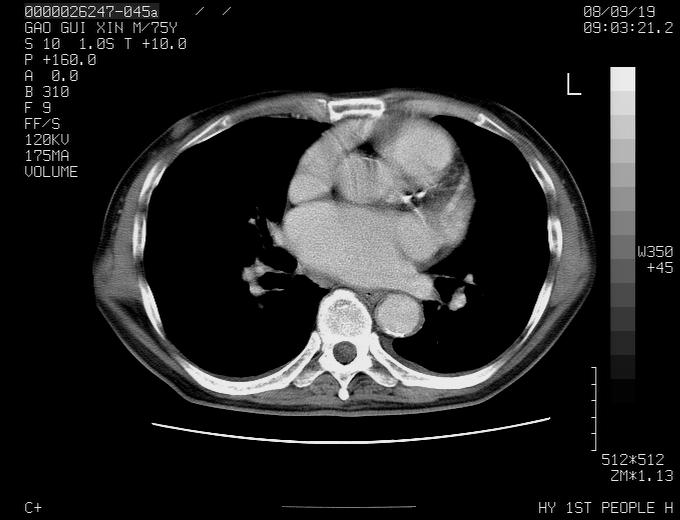

感谢各位老师的意见,左上肺病灶,我本人趋向结核,原因:左上肺见两个类圆形结节,仔细回顾4月份ct似乎原片在该处有条片状密度增高影,强化不明显。

现上传增强片,请各位老师仔细帮我看一下。

右上肺可见条索状影,并可见钙化,左上肺结节可以考虑为结核球,但气管前腔静脉后有肿大淋巴结,本人觉得左上肺结节不能排除转移瘤的可能,右上肺为陈旧性结核灶。

左肺上叶周围性肺癌并纵隔多组lnm.不可能是tb.

左肺上叶尖段瘢痕癌并纵隔淋巴结转移解释更好一些.

1)左肺上叶尖段周围型肺癌并纵隔淋巴结转移。2)冠状动脉及主动脉钙化。